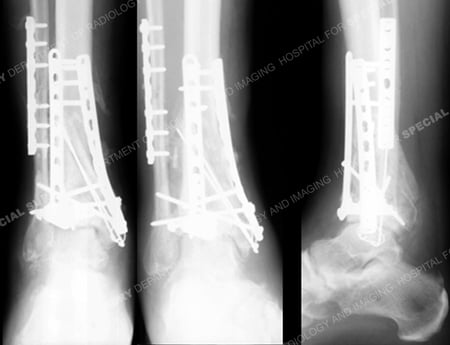

Radiographs at 5 months following the index surgery reveal a healed pilon fracture in excellent alignment

and maintenance of fixation.